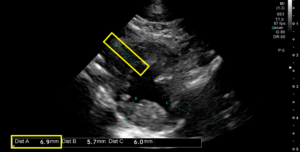

―心臓エコー検査:心筋の肥大、SAM(僧帽弁収縮期前方運動)、左心室内の肉柱を確認。

正常な猫の心筋は6mm以下と言われていますが 、今回の症例では最大6.9mmの肥大が認められました(上画像)。猫の肥大型心筋症は二股のジェット(ジェット気流が二股に分かれているように見える現象)が特徴です(下画像)。